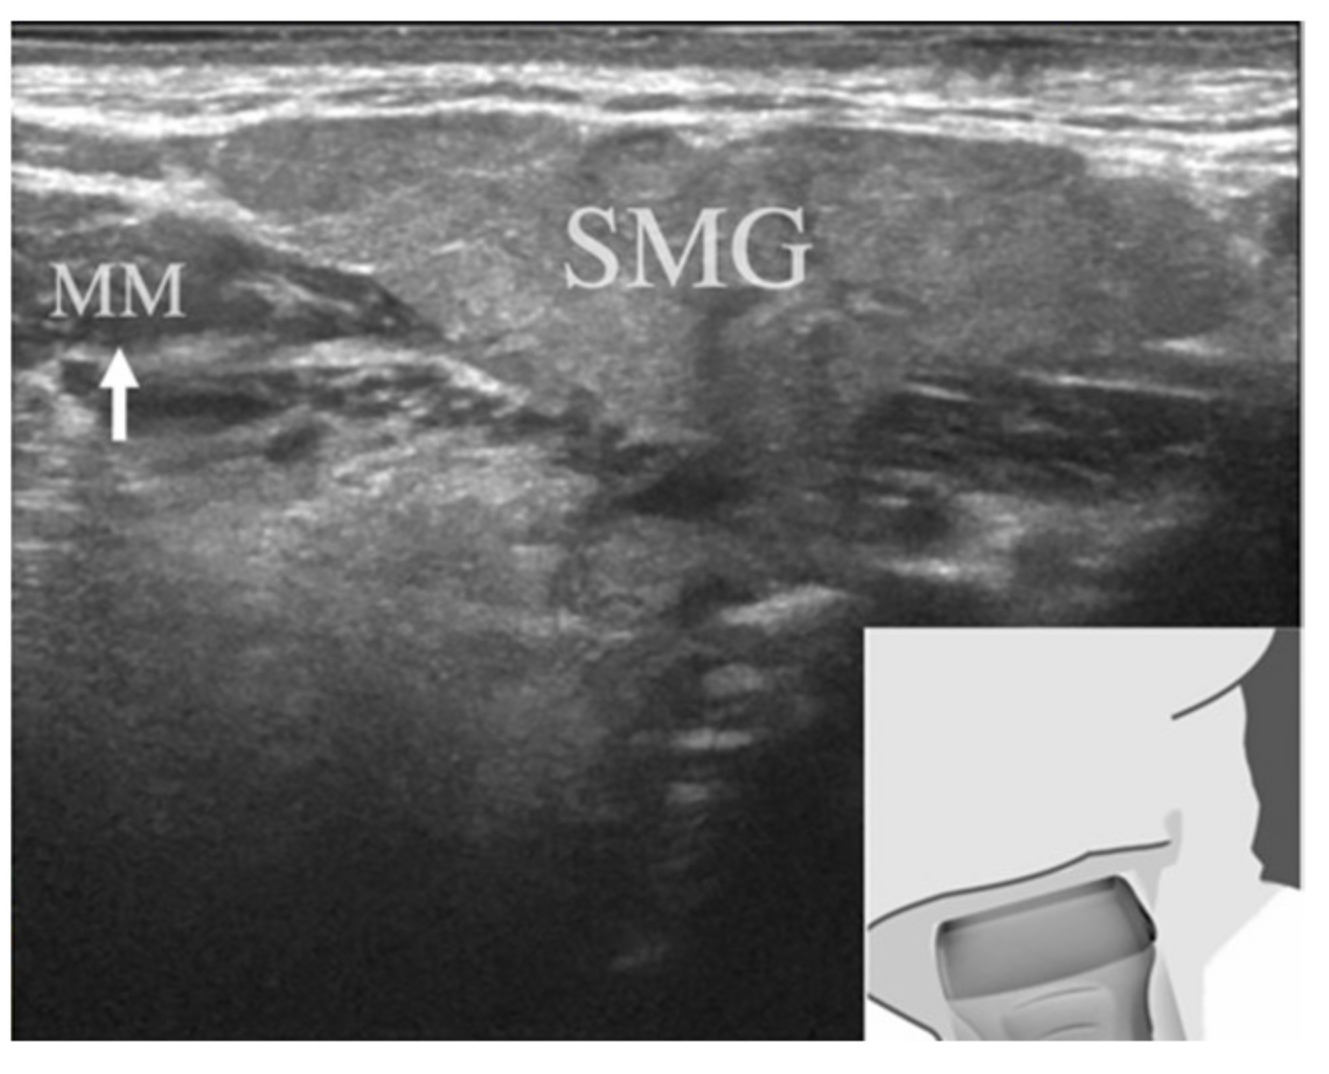

Figure 2.

Illustration of right submandibular gland imaging. The submandibular gland was located in the center of the region of interest, and the mylohyoid muscle was located in the anterior-lower part of the submandibular gland (white arrow). MM, mylohyoid muscle; SMG, submandibular gland.

All USG images of the SMGs were taken in B-mode using a Logiq E9 system (GE Healthcare, Tokyo, Japan) with a center frequency of 12 MHz. The patient was placed in the supine position with his or her neck extended and face directed away from the examination site, and the scan was performed with the sagittal plane parallel to the inferior border of the mandible. The probe was oriented so that the SMG was located in the center of the region of interest and the mylohyoid muscle was located in the anterior-lower part of the SMG (Figure 2). Images of the entire SMG were saved as multiple still images in our hospital imaging database.